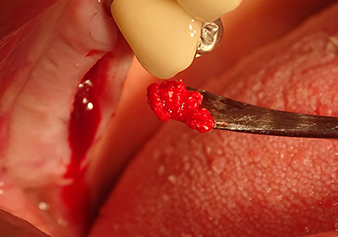

A periosteal elevator is used to place an augmentative mixture carefully into the region of the internal maxillary sinus ostium in the apical direction

Fig.8: A periosteal elevator is used to place an augmentative mixture carefully into the region of the internal maxillary sinus ostium in the apical direction.